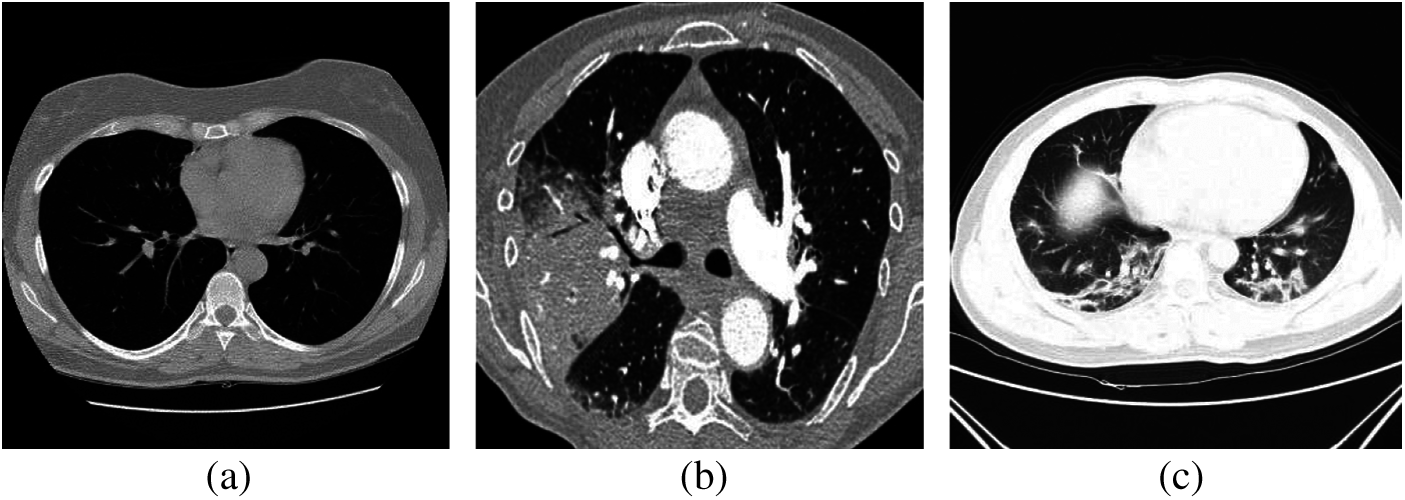

On the other hand, CT imaging was applied in COVID-19 detection cases to show ground glass patterned areas in the images. If these areas are determined accurately, this will help in the process of diagnosis [12–15]. Generally, CT images are generated by collecting several angular projections of X-ray images. The norma, pneumonia, and COVID-19 cases can be detected based on CT images, as illustrated in Fig. 2. Researchers have conducted several approaches by applying medical images using computer vision [16], machine and deep learning [17–19] to automatically diagnose several human body ailments for smart healthcare [20,21]. The recent advanced applications are based on machine learning and artificial intelligence concept to produce proper performance. Deep learning methods have improved the detection accuracy of tumor areas in the lungs, bone suppression by X-ray, diabetic retinopathy, prostate segmentation, skin lesions, and myocardial presence in coronary CT imaging [22–25]. Moreover, deep learning models are generally used for predicting time arrangement to obtain impressive results across diverse fields.

Figure 2: (a) Normal, (b) pneumonia, and (c) COVID-19 CT images